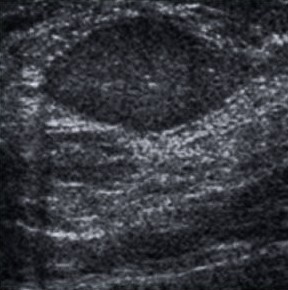

Achados:

- Imagens anecóicas (cistos) com pontos ecogênicos fixos no interior, sugestivas de projeção sólida intracística, ou as imagens anecóicas com espessamento de paredes e septações grosseiras.

- Nódulos sólidos, não-calcificados, ovóides, com orientação paralela à pele, sem achados acústicos posteriores (podem, eventualmente, apresentar discreto reforço posterior) e que ainda não completaram 2 anos de estabilidade.

- Microcistos agrupados: a maioria dos microcistos agrupados representa dilatação cística do ácino com metaplasia apócrina e não apresenta sinais de malignidade.

- Cistos com conteúdo espesso: nódulos hipoecóicos redondos ou ovóides, com ecos homogêneos no interior.